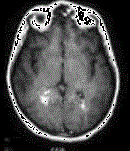

问题 男性,40岁,因感冒半月后出现性情改变如欣快、暴躁和猜疑,以及EEG弥漫性慢波,以脑炎诊断住院20天,经治疗病情明显好转,准备3日后出院。但患者病情反复,MRI如图,应考虑 ( )

选项 A、脑干肿瘤 B、脊髓压迫症 C、重症肌无力 D、多发性硬化 E、球后视神经炎

答案 D